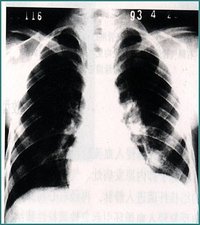

血行播散型肺結核急性粟粒型結核是急性全身血行播散型結核病的一部分,起病急,有全身毒血症狀,常伴髮結核性腦膜炎,X線顯示雙肺在濃密的網狀陰影上,滿布境界清晰的粟粒狀陰影,直徑約2mm,大小及密度大體相等。病初胸片可能無明顯粟粒狀影,或僅僅有關瀰漫性網狀改變易誤診為傷寒、敗血症等其他發熱性疾病。若人體抵抗力較強,少量結核菌分批經血液循環進入肺部,其血行播散灶常大小不均勻、新舊不等,在雙肺上中部分部呈對稱性分布,稱為亞急性過慢性血行播散型肺結核。其病情發展緩慢,通常無顯著中毒症狀,患者可無自覺症狀,偶於X線檢查時才被發現。此時病灶較穩定或已硬結癒合。

2、影像學檢查胸部X線檢查可以發現肺內病變的部位、範圍,有無空洞或空洞大小,洞壁厚薄等。X線對各類結核病變的透過度不同,通過X線檢查大致能估計結核病灶的病理性質,並能早期發現肺結核,以及判斷病情發展及治療效果,有助於決定治療方案。必須指出,不同病因引起的肺內病變,可能呈現相似的X線影像,故亦不能僅憑X線檢查輕易確定肺結核的診斷。X線攝片結合透視有助於提高診斷的準確性,可發現肋骨、縱隔、膈肌或被心臟遮蓋的細胞病灶,並能觀察心、肺、膈肌的動態。肺結核的X線表現包括:纖維鈣化的硬結病灶,表現為密度較高、邊緣清晰的斑點、條索取或者結節;浸潤性病灶,表現為密度較單,邊緣模糊的雲霧狀陰影;乾酪樣病灶,表現為密度較高,濃淡不一,有環形邊界透光區的空洞等。肺結核病灶通常在肺上部、單側或雙側,促成時間較長,且有多種不同性質的病灶混合存在及肺內播散跡象。凡X線胸片上顯示滲出性或滲出增殖性病灶、乾酪樣肺炎、乾酪樣病灶、空洞(除淨化空洞外),均提示為活動性病變;增殖性病變、纖維包裹緊密的乾酪硬結灶火及纖維鈣化灶等,均屬非活動性病變。活動性病灶的痰中仍可找到結核菌。由於肺結核病變多為混合性,在未達到完全增殖或纖維鈣化時,均仍應考慮為活動性。肺部CT檢查對於發現微小或隱蔽性病變,了解病變範圍及肺病變鑑別等方面均有幫助。

4.x 線胸片兩肺見典型粟粒陰影 。胸CT急性血行播散型肺結核表現為直徑1-3mm大小、密度及分布均勻的粟粒結節;而亞急性和慢性患者表現以上中肺野為主的3-7mm大小、密度及分布不均勻的結節。結節的邊界多數尚清晰,但也有表現邊界模糊;結節隨機分布於肺小葉、小葉間隔及胸膜下。